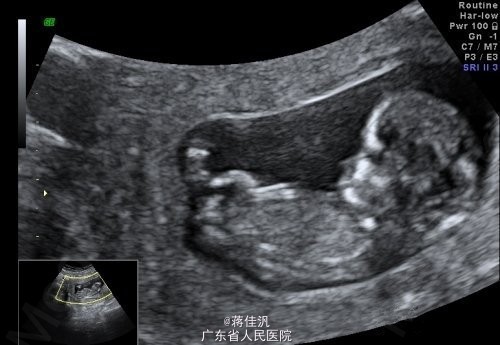

T:36.8℃,BP:170/115mmHg。 专科检查:宫高29cm,腹围86cm,胎位LOA,胎心150/min,未触及敏感宫缩。双下肢膝关节以下非凹陷性水肿。 辅助检查:血常规:WBC 4.6*10^9/L,RBC 4.28*10^12/L,HGB 146g/L,PLT 162*10^9/L,LYM% 0.288,GRAN% 0.682。CRP、PCT正常。子宫双附件B超示:宫内妊娠单活胎,相当于孕33周。胎监9分。尿常规示:尿蛋白(3+)。